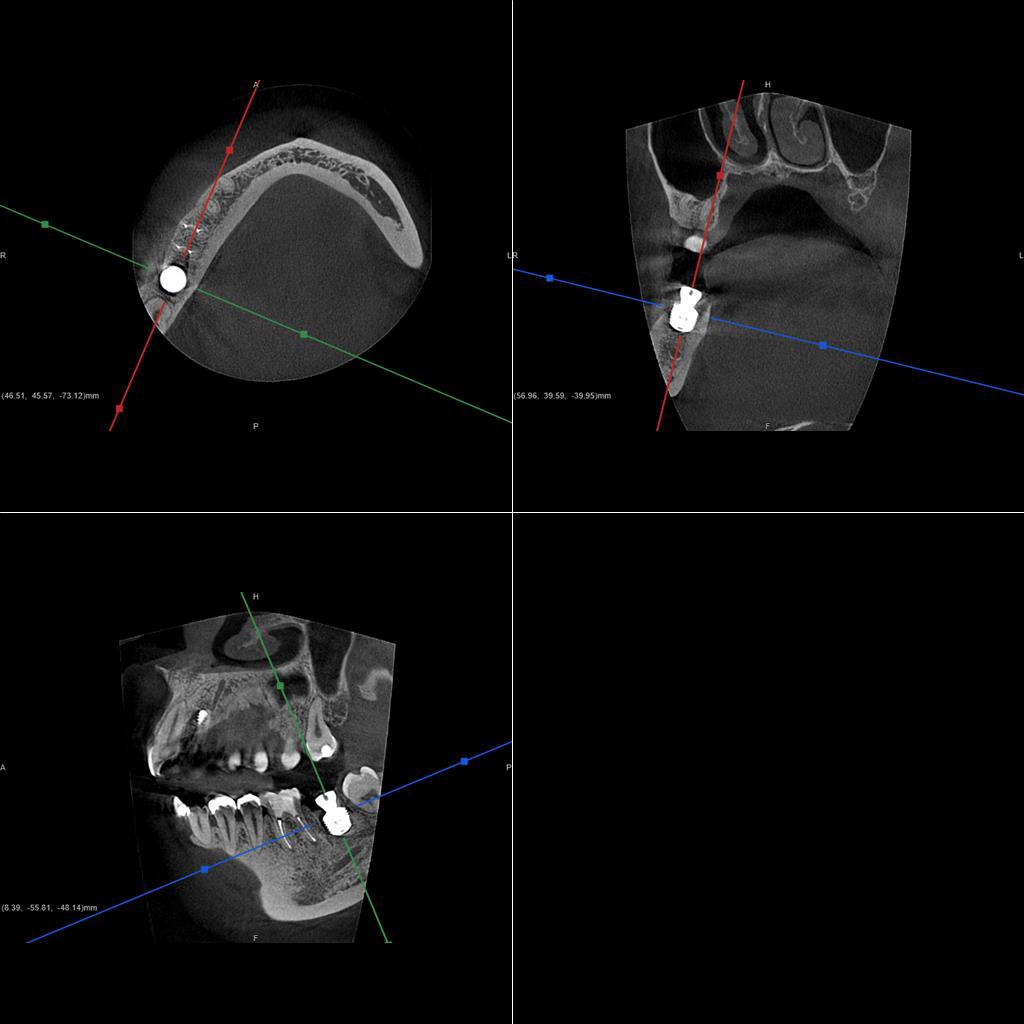

| 診断結果 | 右下7番歯根破折 |

| 治療内容 | 抜歯即時インプラント |